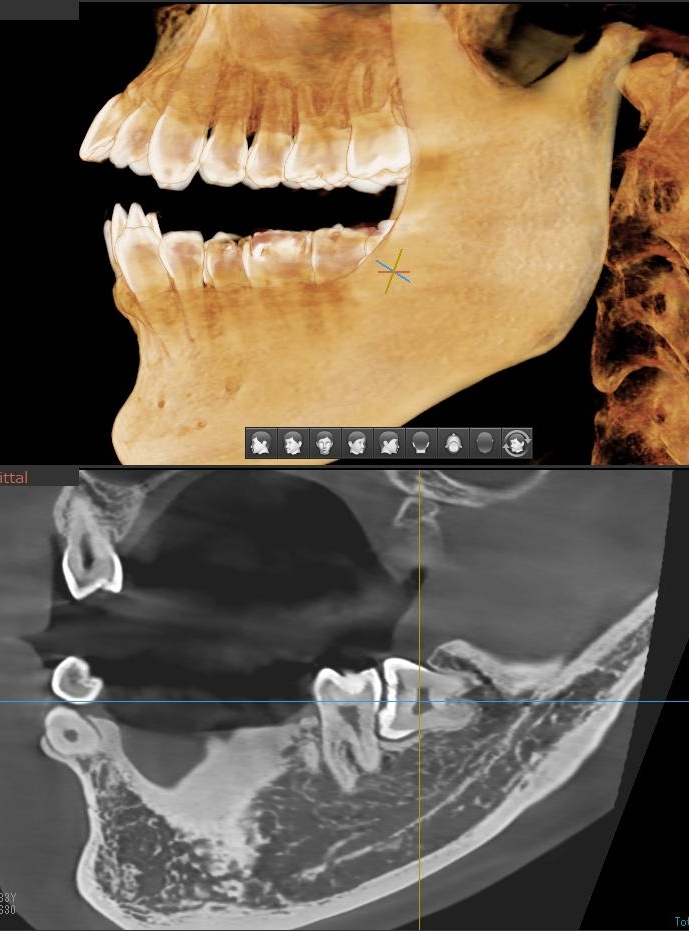

次にパノラマ写真を撮影してみると、左下の親知らずは手前の歯と並んでまっすぐに生えているのが確認できました。

さらに、下顎の親知らずは下歯槽神経に非常に近いところに生えている場合もあるため、CTも撮影し詳しい解析を行います。

親知らずが生えている位置が、神経に近い、あるいは神経に当たっている場合は、大きな病院に紹介する場合もあります。

親知らずの根っこは下歯槽神経から近い距離にありますが、抜歯は可能との診断でした。